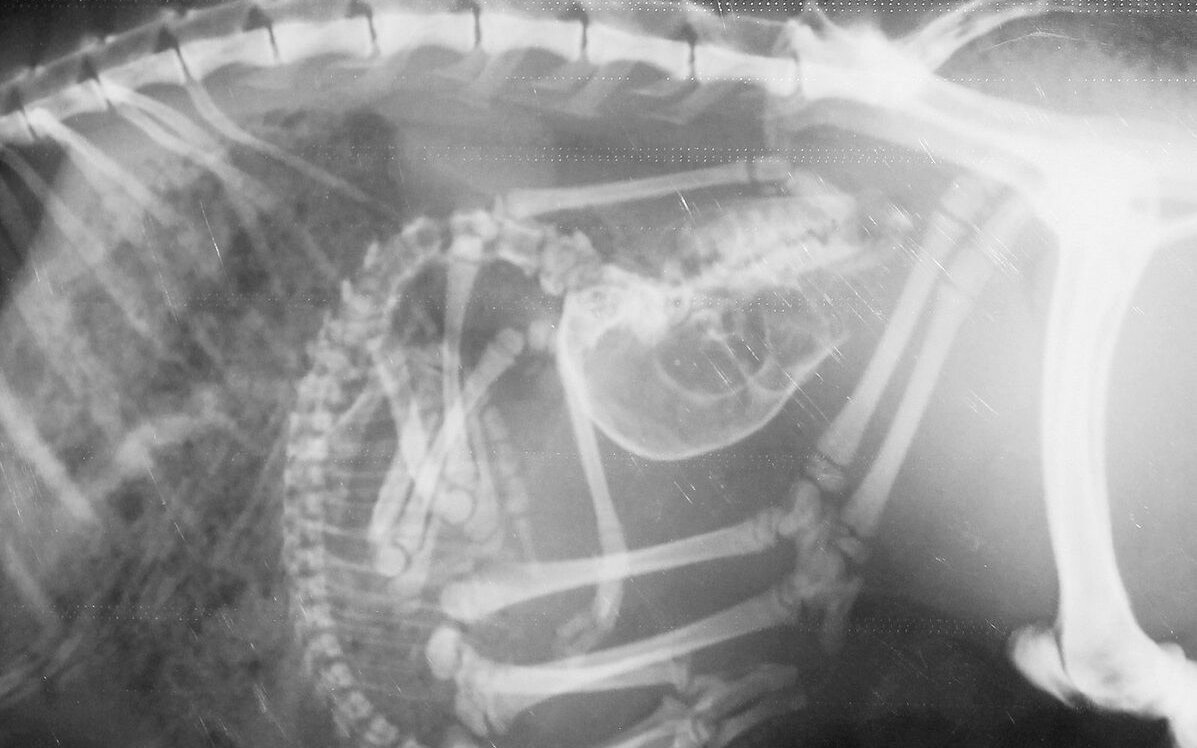

Einfacher auf dem Röntgentisch fixiert werden als ein Fisch kann eine Schildkröte. «Wir setzen sie auf eine Platte», sagt Christian Wenker. Bevor sie den Kopf aus dem Panzer schiebt, ist das Röntgenbild schon gemacht. Wie bei Vögeln kommt bei Reptilien Legenot vor, die mittels eines Röntgenbildes festgestellt werden kann. Damit Echsen wie Leguane nicht von der Röntgenplatte krabbeln, gibt es einen Trick. «Wir drücken kurz sanft und gleichzeitig auf die Augäpfel, dies führt über einen Vagusreflex zu einem betäubungsähnlichen Zustand», sagt der Zootierarzt.

[IMG 5]